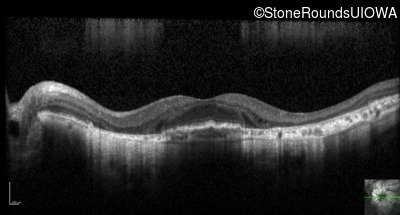

Optical Coherence Tomography - Right - 20/40 -2

Exemplar / OCT Stack

OCT Stack